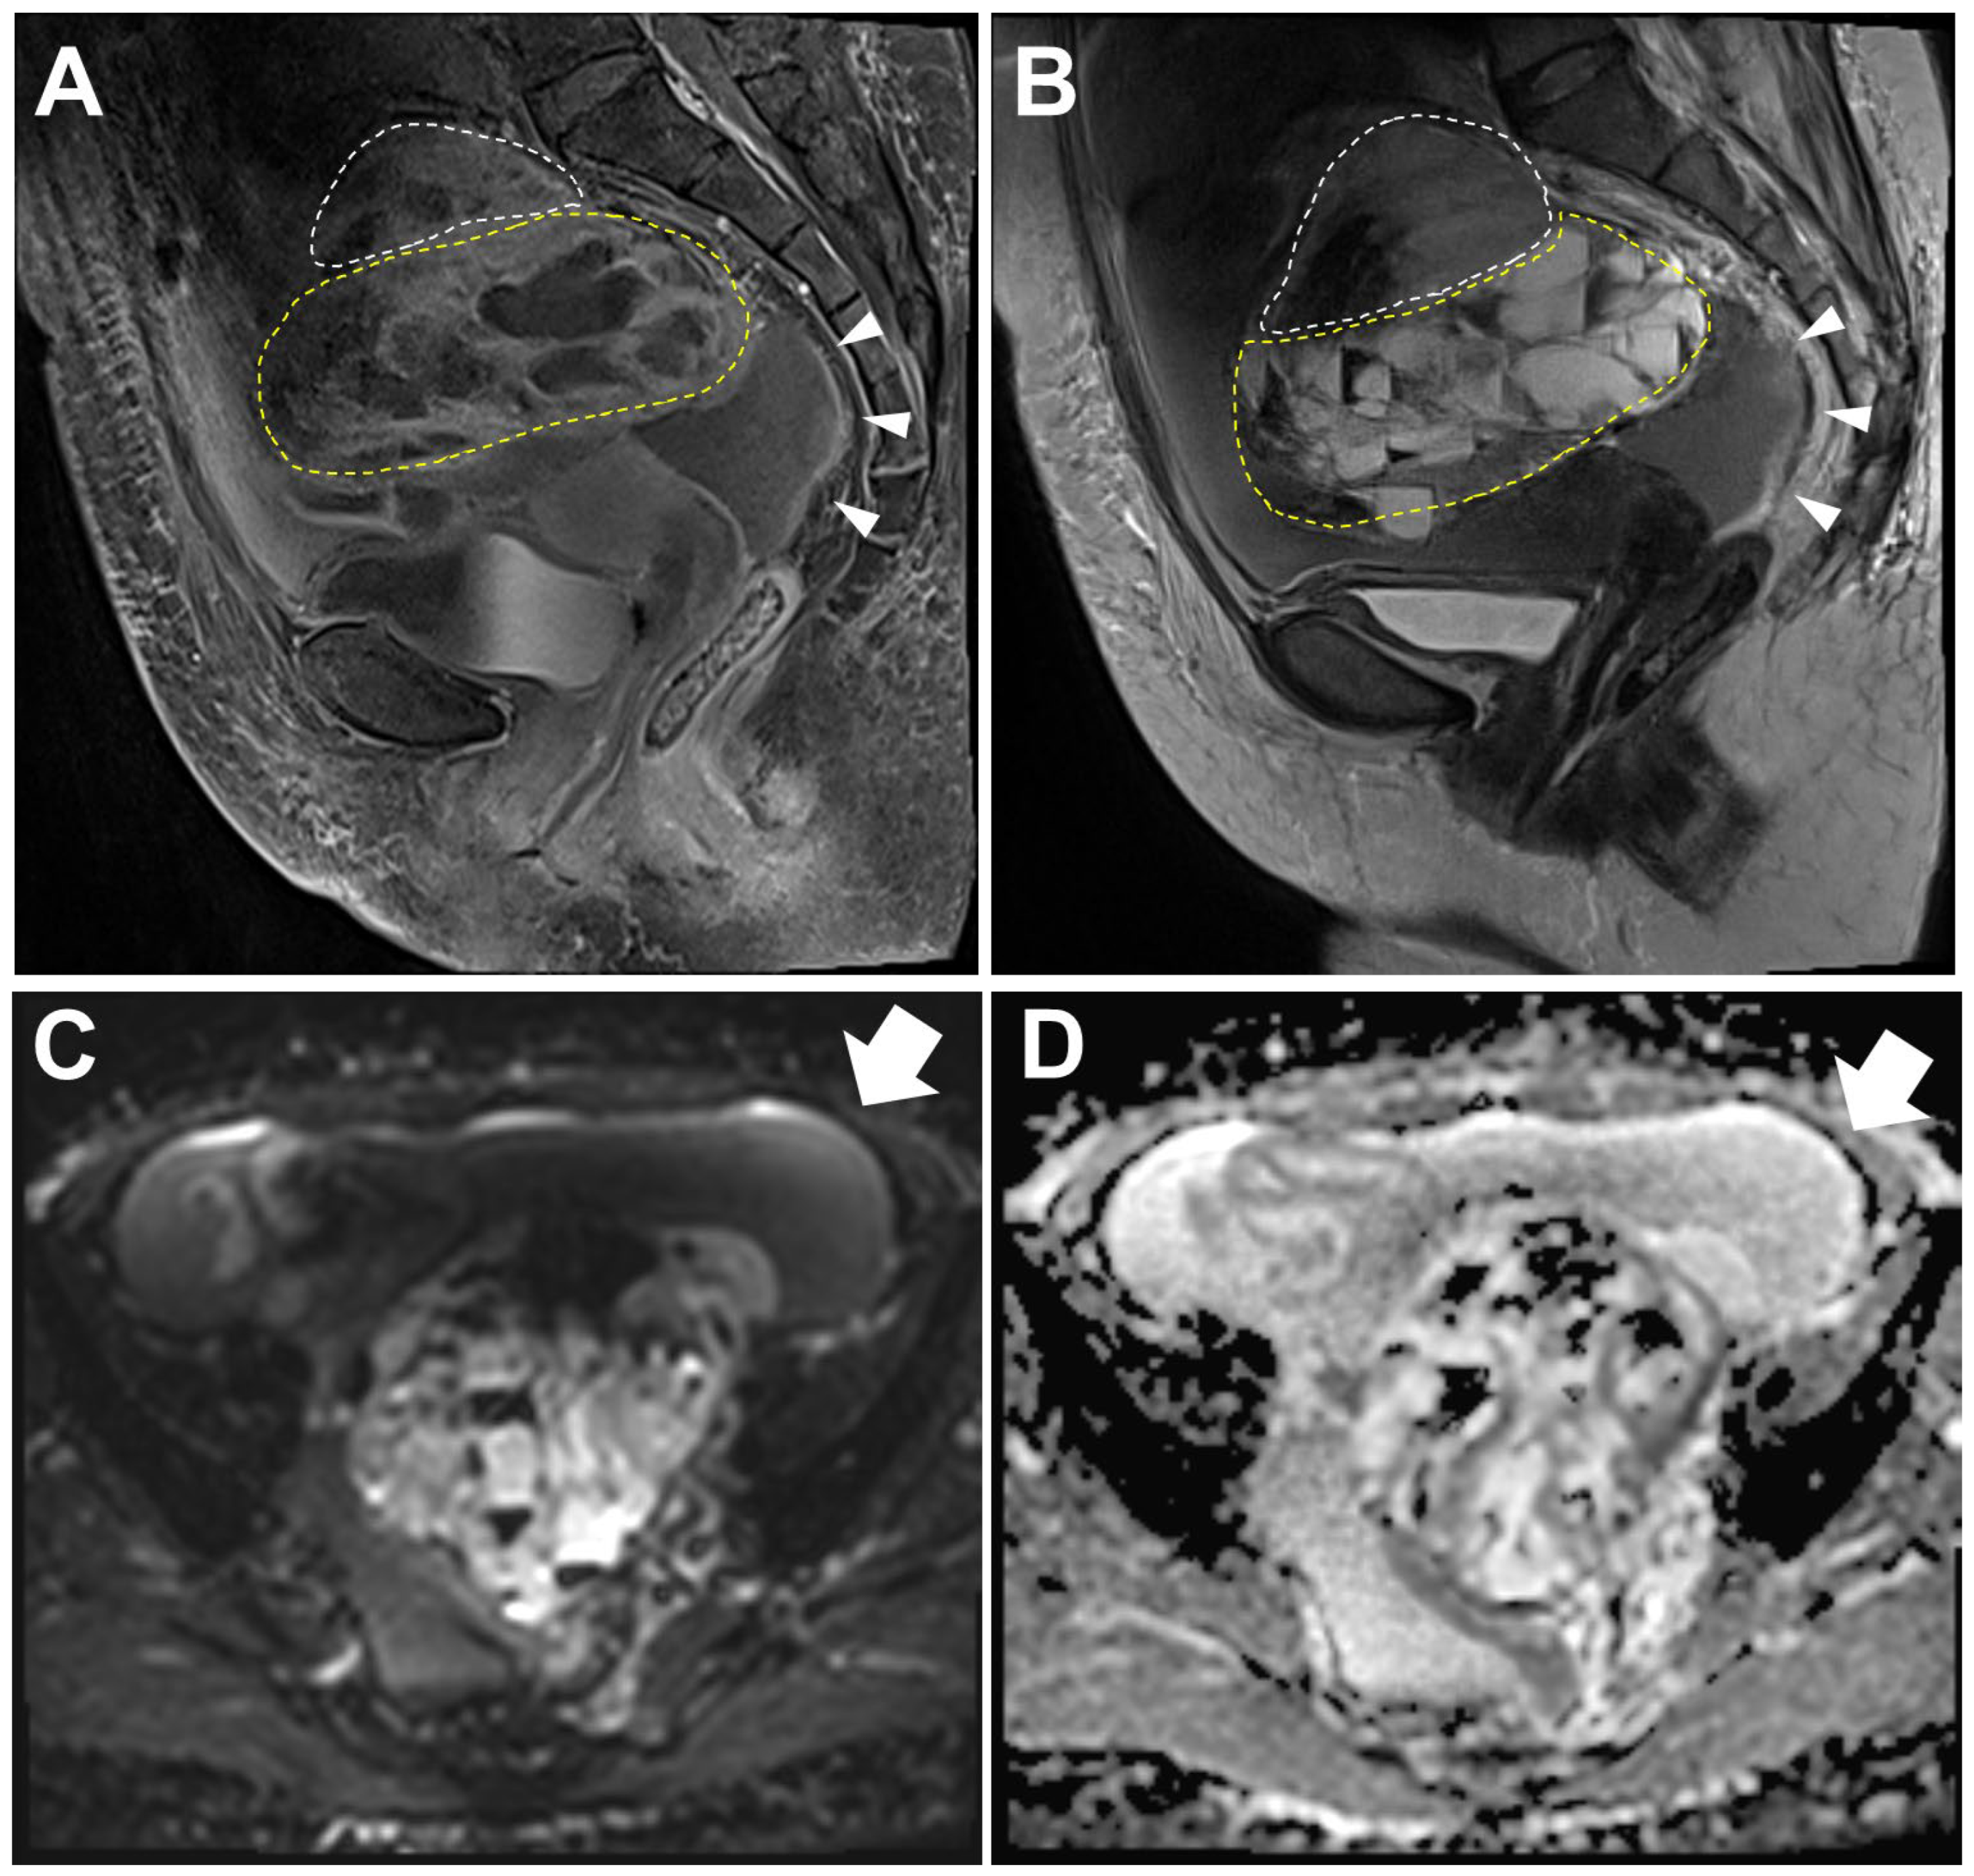

Magnetic resonance imaging (MRI) of the pelvis. Sagittal fat suppression T1-weighted (A) and T2-weighted (B) images revealed a multiloculated cyst with watery fluid or internal hemorrhage in the left ovary measuring 11.7 cm in size (anterior–posterior extension: 11.1 cm, width: 10.5 cm, oblique craniocaudal extension: 11.7 cm). Based on the multilocular cystic appearance with a macrofollicular pattern filled with watery fluid or hemorrhage, the impression was an adult granulosa cell tumor (AGCT) [1,2,3] and endometrioid carcinoma [4]. A solid component was noted at the cranial side (white dashed line) of the mass, measuring 5.4 cm in size (anterior–posterior extension: 4.0 cm, width: 5.4 cm, oblique craniocaudal extension: 3.5 cm). In this area, fat suppression T1-weighted images exhibited enhancement resembling that of a multilocular cyst (yellow dashed line), whereas the T2-weighted images showed a comparatively lower level of enhancement. In addition, peritoneal thickening was shown (arrowheads). Diffusion-weighted image (C) and apparent diffusion coefficient map (D) showed ascitic fluid without diffusion restriction (arrow).

Collision tumors of the ovary [5,6,7,8,9,10,11,12,13,14,15,16] are very rare, making their inclusion in differential diagnosis challenging in routine clinical practice. Moreover, ovarian cancers often present with heterogeneous components, so the presence of both solid components and multilocular cysts is not unusual [4,17]. However, in the present case, the enhancement in the solid component in the T2-weighted images was lower than that in the multilocular cystic area. The same part of the tumor usually shows similar enhancement patterns [2,3,4,14,15,16]; therefore, the possibility of a collision tumor was suspected.

A 63-year-old woman visited our outpatient clinic with a left ovarian mass found on an external computed tomography scan. The symptoms at presentation included abdominal discomfort. Preoperative laboratory test results for serum CA125 and CA19-9 levels were within the normal range (10.6 U/mL and 8.73 U/mL, respectively). The patient underwent a Papanicolaou test of routine screening one year ago at an external hospital, which yielded a negative result. An MRI examination was requested for a diagnostic work-up (Figure 1), and a left ovarian mass and a large amount of ascites with mild peritoneal thickening were observed. Ascites may be attributable to a partial mass rupture and hemoperitoneum, and it was necessary to consider this as an early finding indicative of potential peritoneal seeding. The patient underwent a total hysterectomy with bilateral salpingo-oophorectomy, omentectomy, and lymph node dissection. Pathologic examination was performed for the diagnosis.